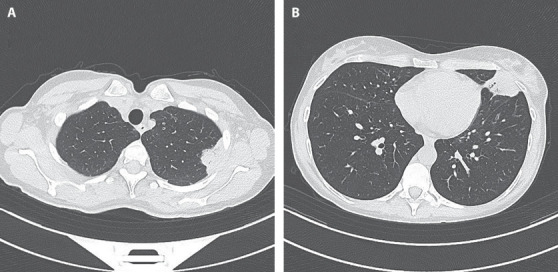

Primary Sjögren syndrome (pSS) is a systemic autoimmune disorder that principally affects the exocrine glands but can also affect systemic or extra-glandular sites. Approximately 65-80% of patients with Sjogren's demonstrate pulmonary involvement at the CT scan and pulmonary nodules (PNs) can be encountered as a common finding. We present the case of a 49-year-old woman admitted to the emergency department for chest pain and fever. The patient was diagnosed with pSS fourteen years prior and had never taken therapy or followed regular check-ups. At the HRTC were found PNs that were studied trough a CT-PET and a needle biopsy via CT guidance, which showed diffuse large B cell lymphoma. This case report underlies the importance of check-ups and the need for a multidisciplinary approach in the care of Sjögren's syndrome patients.